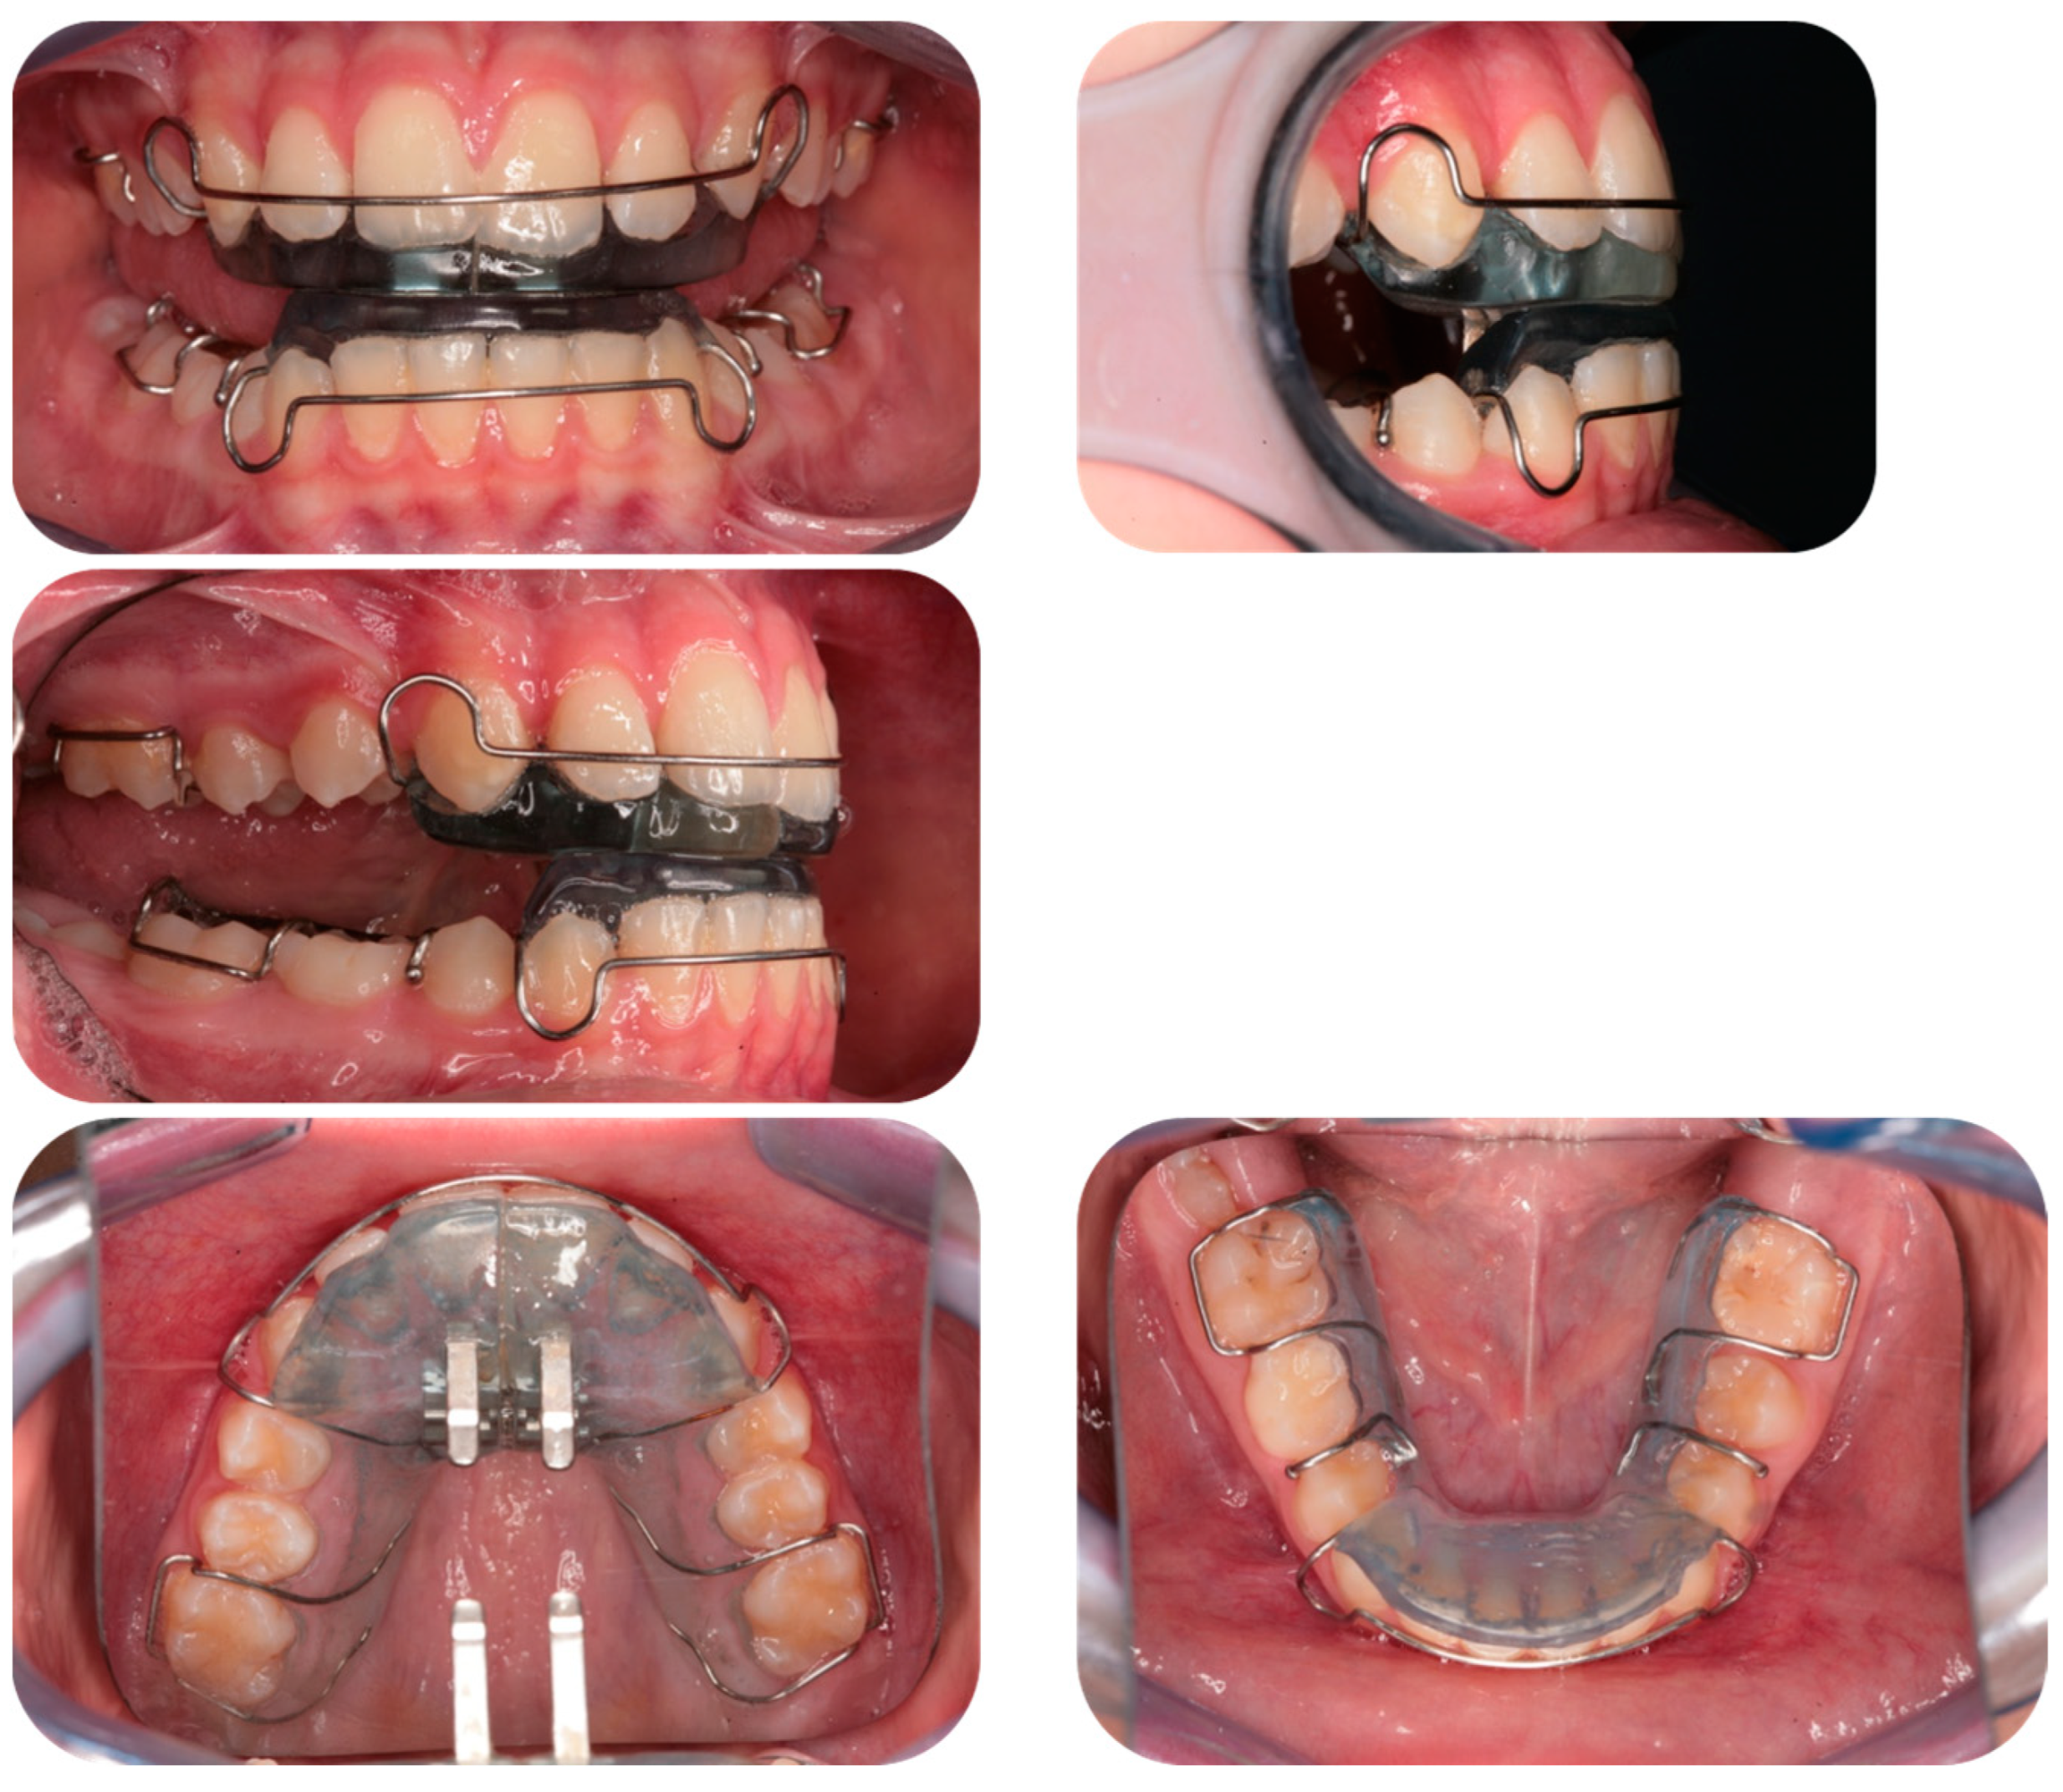

- The bite was prepared using five layers of wax (three layers of hard wax with two layers of soft wax in between).

- The jaw of the patient, seated and in a relaxed position, was guided into the established position 3–4 times by manipulating the chin between the thumb and forefinger; the patient then repeated the same exercise while keeping the jaw in an advanced position for a few minutes.

- The wax, once softened, was then placed in the patient’s mouth, and the mandible was guided into the desired closed position by checking the butt-to-butt incisal ratio, the Class I or overcorrected Class I molar ratio, and the midline.

- The wax was removed, checked on the models, and the edges were trimmed, cooled, and checked again in the mouth.